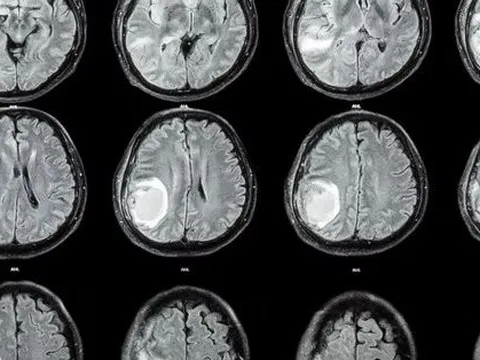

Đầu bé 1 tuổi tự nhiên to lên, bác sĩ lấy ra cả một bào thai trong não

Ca bệnh đặc biệt được công bố trên tạp chí Neurology được xác nhận là một trường hợp thai trong thai cực hiếm, trong đó đứa bé ra đời đã mang theo bào thai người em song sinh trong não.